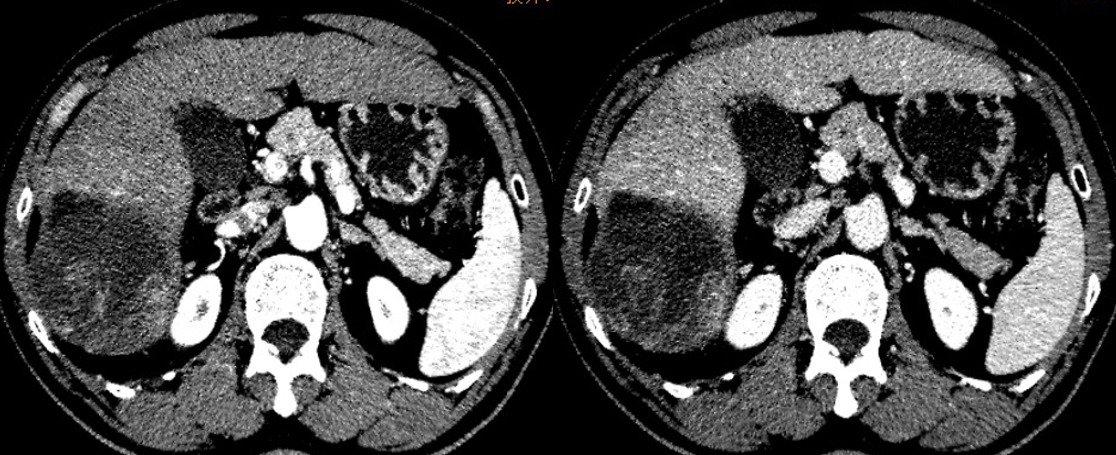

上腹CT:

2018年7月2日

肝右叶巨块型肝细胞癌

肿瘤最大径18cm

门静脉受压,未见癌栓形成

2018年12月11日复查CT:肝右叶肿瘤较前缩小,肿瘤坏死面积较前稍增加。